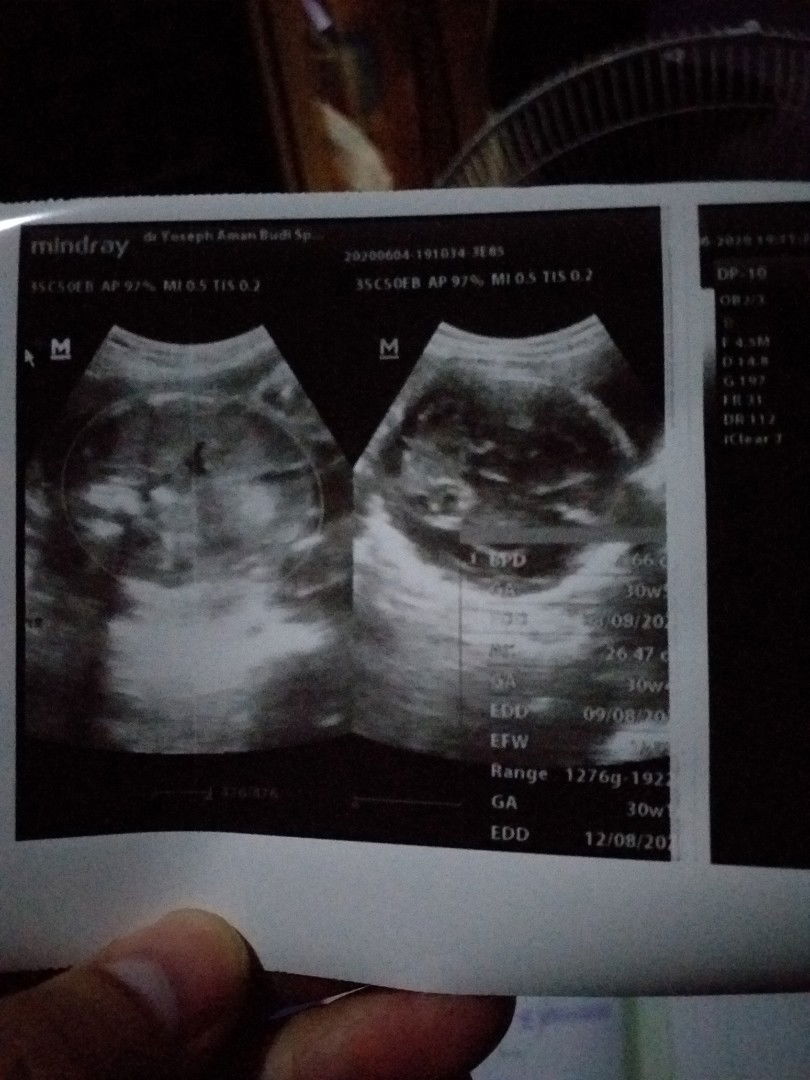

Alhamdulillah sudah usg y walaupun bukan yg 4d karena efek pandemi jadi malas ke rs jadi k klinik dekat rumah saja. Posisi janin kepala sudah dibawah. Bbj 1,6 normal untuk uk 30w, detak jantung dan ketuban cukup. Hpl bidan dan usg akur 12 agustus. Jk sesuai dengan feeling ibu dan keinginan suami. Tinggal jaga kesehatan ibu dan bayi sampai waktunya lahiran. Semoga semua bunda diberi kenikmatan yg sama sampai waktunya ketemu dd. Amin

Alhamdulillah udah usg y walaupun g yg 4d efek pandemi males k rs jadi k klinik yg dekat saja. Posisi janin kepala sudah dibawah. Hpl bidan sama usg akur 12 agustus. Ketuban cukup, detak jantung bagus, bbj 1,6 normal untuk uk 30w. Tinggal jaga kesehatan sampai waktunya melahirkan. Semoga semua bunda juga diberikan nikmat yg sama lancar sampai waktunya ketemu dd. Amin